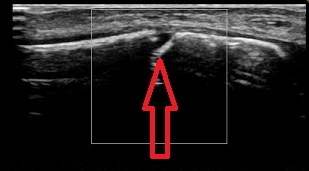

3.小学校5年生の腓骨下端部(外くるぶし・矢印が骨端線)